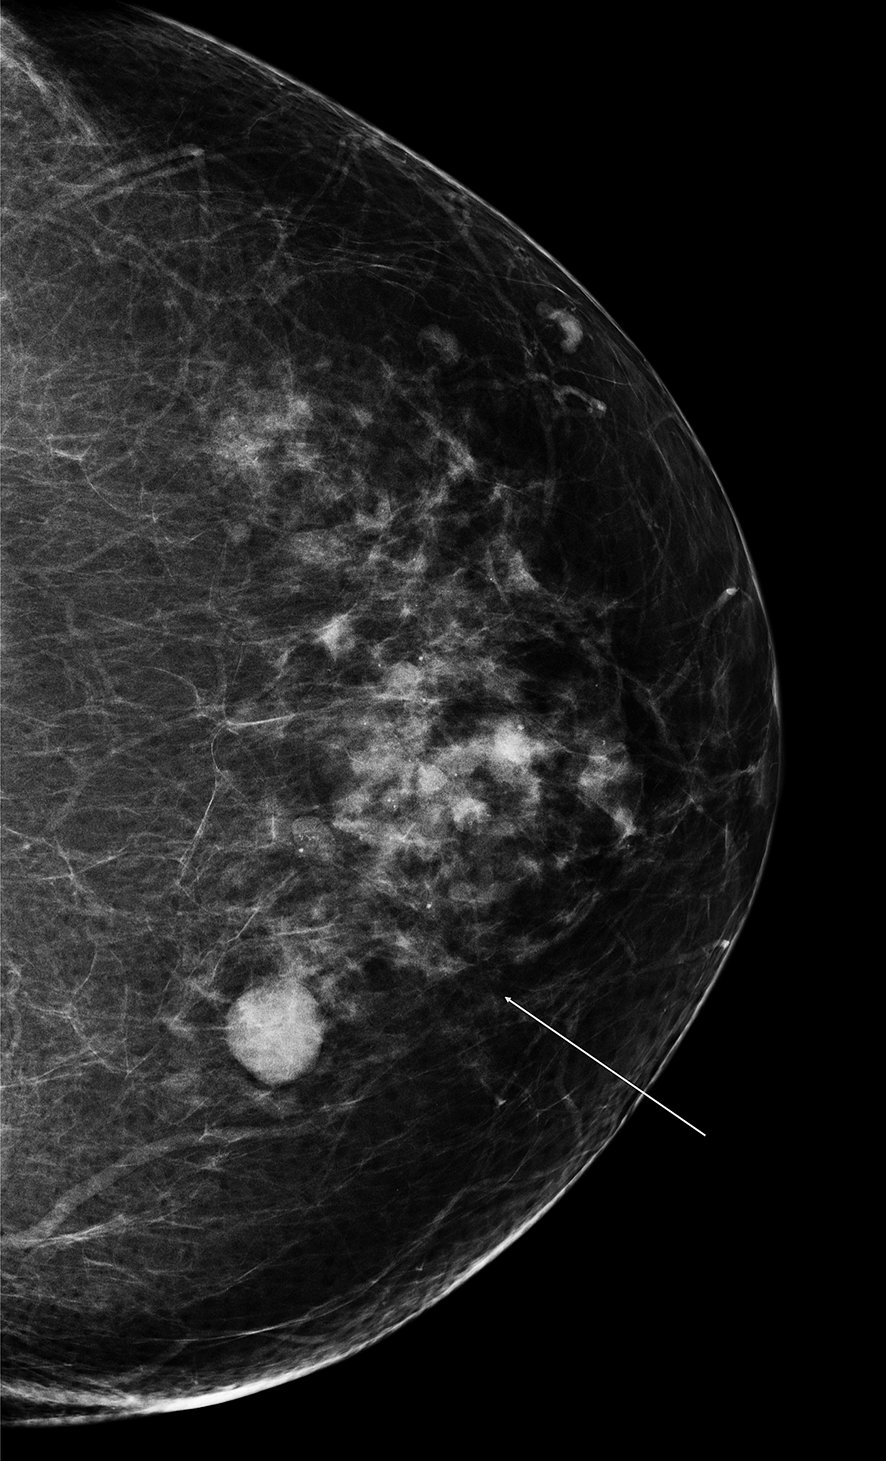

Figure 20.6 Aspect mammographique d’un kyste (opacité arrondie, à contours nets)